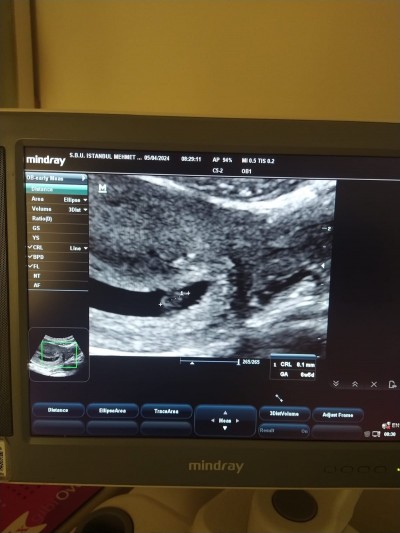

Arkadaşlar doktor ikiz veya tekil gebelik diye bilgilendirme yapmadı ama resme bakınca iki ayrı kese ve keselerin içinde beyaz nokta var gibi. Gazım veya idrarım okdupundan keselerin şekli ince gibi geldi bana. Sizcede iki ayrı kese ve iki ayrı bebek yok mu? Resmi ekliyorum

Yok hayır ikiz değil ben ikiz gebeyim burda 2 nokta derken neyi kasteddin onu bile göremedim

Diğeri kese değil. Eğer kese olsaydı doktor mutlaka söylerdi.